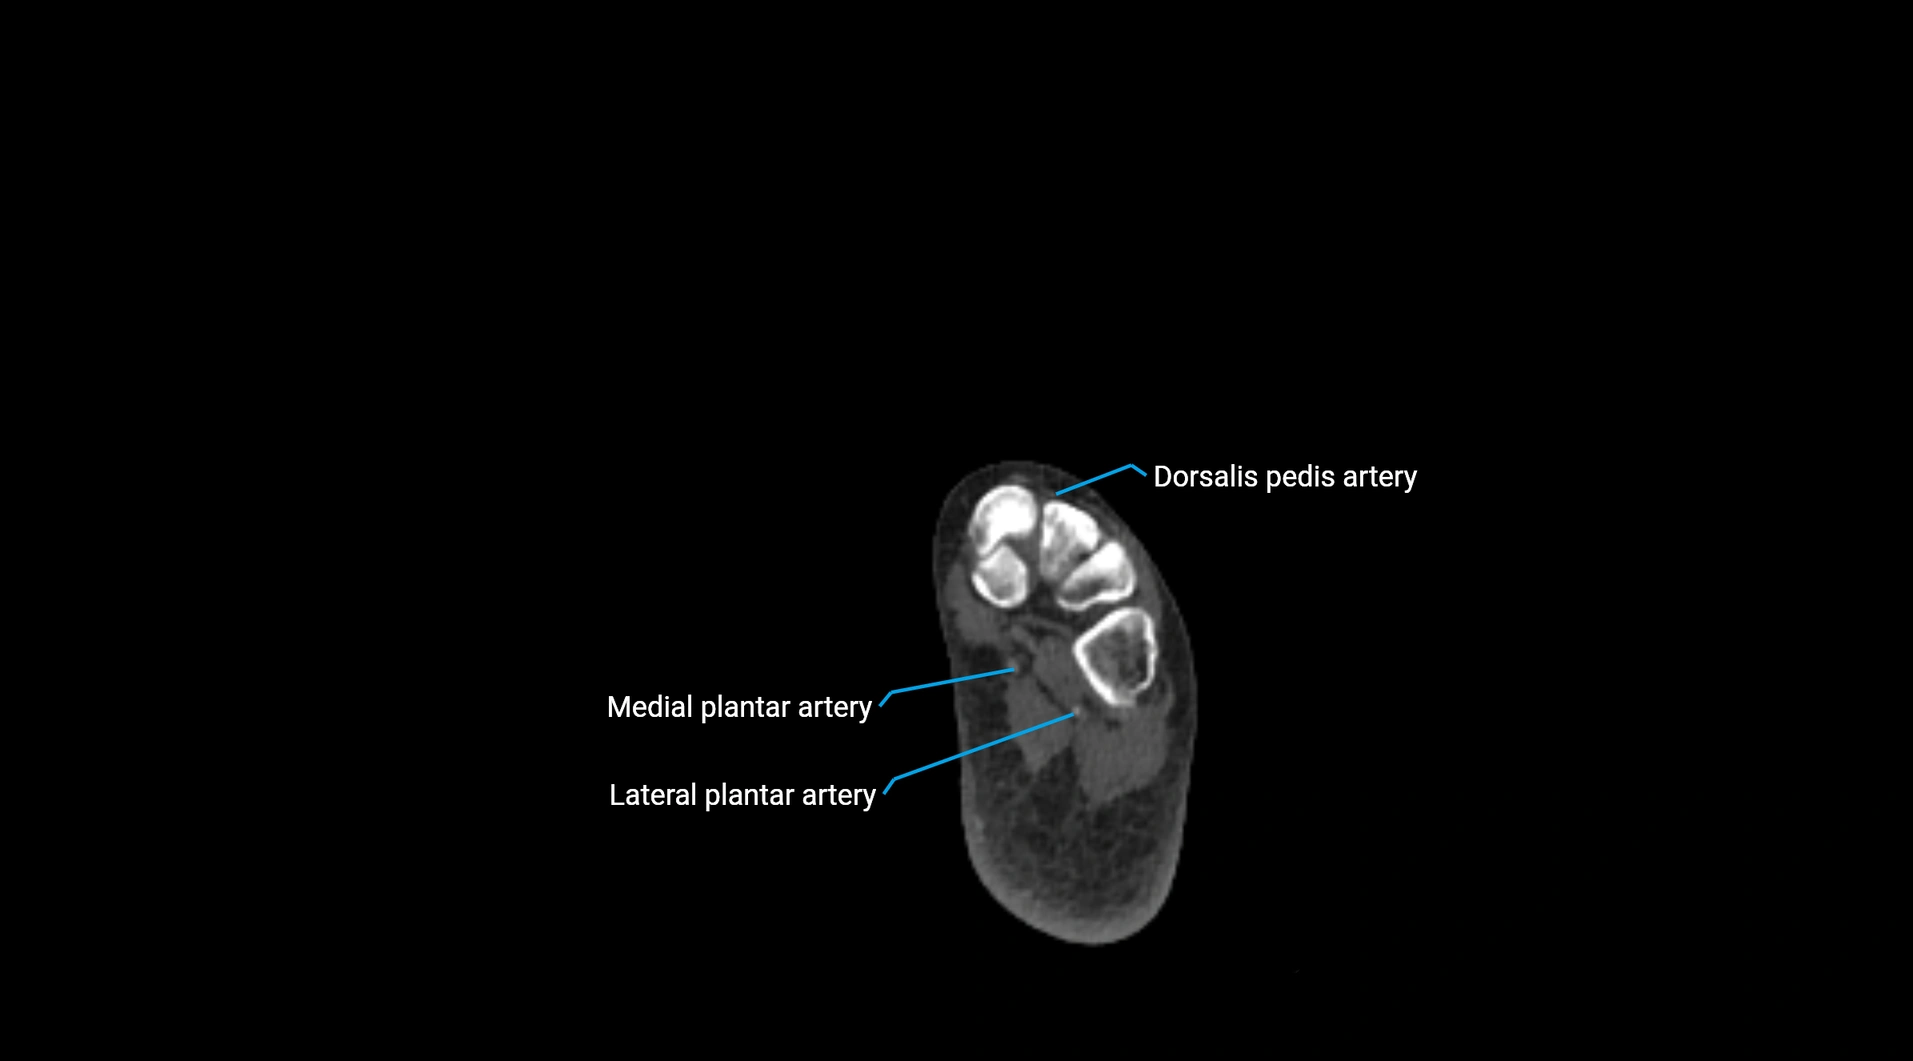

CT images

image

Contrast-enhanced CT (CTA):

• Gold standard for abdominal aortic imaging

• Provides excellent detail of lumen, wall, aneurysm, thrombus, and branch vessels

• Multiplanar and 3D reconstructions help in aneurysm measurement, stent graft planning, and dissection evaluation